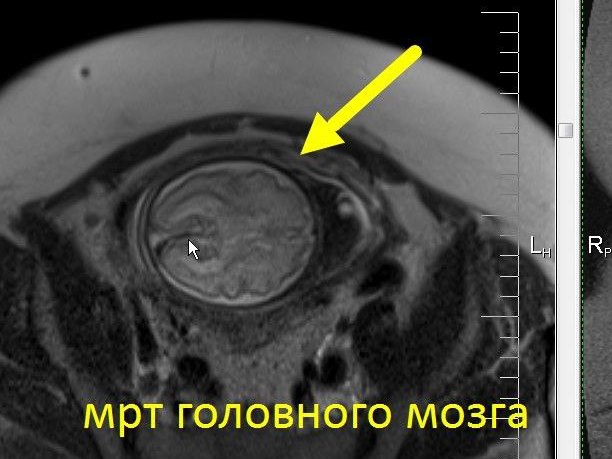

Заблуждения и факты о внутрибрюшной беременности